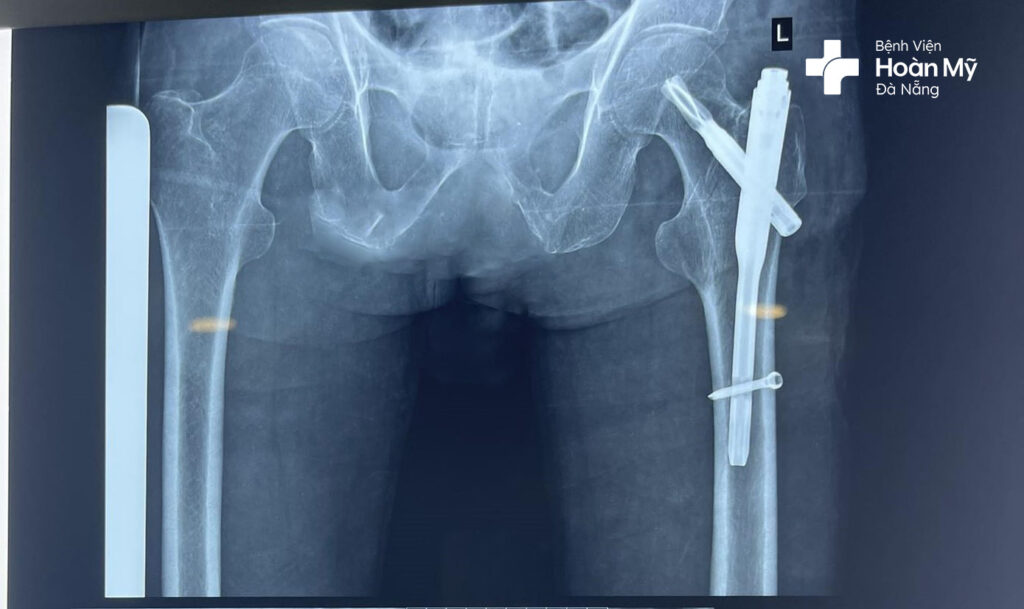

Hình ảnh kết hợp xương bằng đóng đinh nội tủy sau phẫu thuật cho người bệnh

Ca phẫu thuật được thực hiện thành công sau 40 phút tiến hành với vết mổ nhỏ 2-3 cm, người bệnh ít mất máu.

Ở ngày thứ 1 sau phẫu thuật, người bệnh đã bắt đầu với các bài tập phục hồi chức năng, tập đi lại. Đến ngày thứ 3, người bệnh đã có thể tự đi lại với khung tập đi, không cần người hỗ trợ. Ngày thứ 5, người bệnh được cho xuất viện.